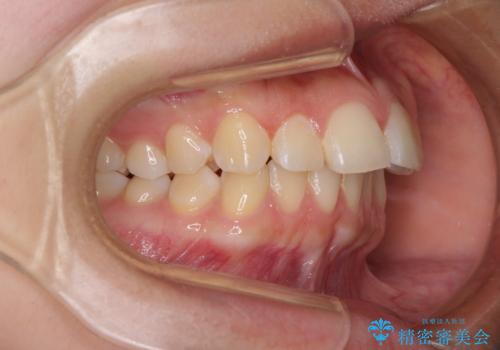

- 前歯の叢生を気にして来院された患者様です。

奥歯の咬み合わせを見ると、上顎が下顎に対して相対的に前方にあり、上下の前歯が接触していない状態でした。

咬み合わせを改善するためには、上顎臼歯を後方に移動させた咬み合わせにする必要があります。

インビザライン単体で改善することも可能ですが、咬合力が強く、単位で達成する可能性が低いと考えられたため、カリエール・ディスタライザーという補助装置を併用して、より確実性を上げることとしました。

奥歯の咬み合わせを改善しながら、並行してインビザラインで歯列を整えることとしました。